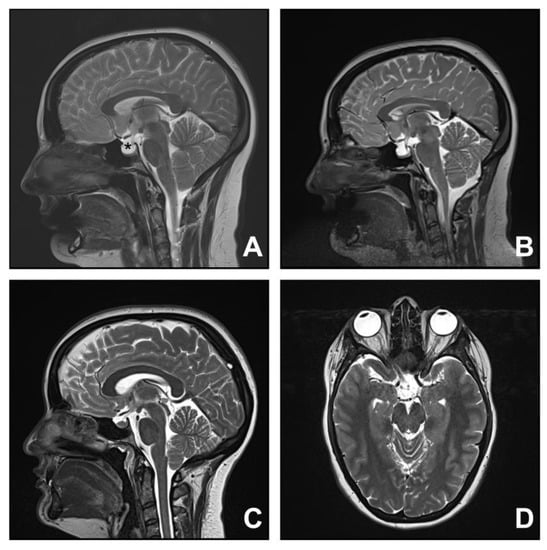

3.3. Group Three. Spontaneous Intracranial Hypotension

| 5 | 49 | F | Headache | 8 | Pachymeningeal enhancement Brain sagging | Blood patch | Improved |

| 6 | 73 | F | Headache | 1 | Brain sagging | Blood patch | Improved |

| 7 | 47 | F | Headache | 5 | Brain sagging | Thoracic laminectomy for CSF leak | Improved |

| 8 | 52 | F | Headache | 2 | Pachymeningeal enhancement, pituitary gland engorgement | Blood patch Thoracic laminectomy for CSF leak | Improved |

| 9 | 51 | F | Headache | 8 | Pachymeningeal enhancement, venous sinus engorgement, brain sagging, syrinx | Multiple surgical decompressions Shunt insertion and revision for syrinx Thoracic laminectomy for CSF repair | Improved |

| 10 | 68 | F | Headache | 2 | Pachymeningeal enhancement, venous sinus engorgement, brain sagging, syrinx | Blood patch | Stable |